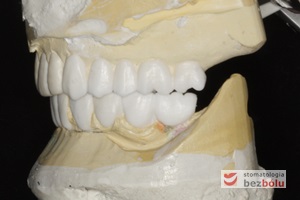

Gotowa praca protetyczna - korony cerkonowo-ceramiczne na modelu roboczym dostarczone z laboratorium protetycznego

Gotowa praca protetyczna – korony cerkonowo-ceramiczne na modelu roboczym dostarczone z laboratorium protetycznego